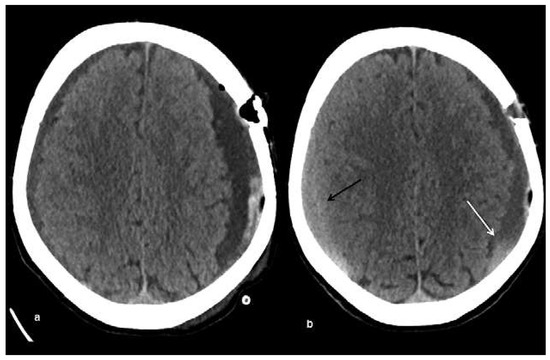

Head and brain trauma: general aspects and neuroimaging

by Johanna Maria Lieb, Christoph Stippich and Meritxell Garcia

In this article the general clinical aspects, imaging indications and different injury mechanisms of traumatic brain injury (TBI) are reviewed. In addition, the different imaging modalities and strategies are presented, including more specific imaging features of the various injuries. Computed tomography (CT) is [...] Read more.

In this article the general clinical aspects, imaging indications and different injury mechanisms of traumatic brain injury (TBI) are reviewed. In addition, the different imaging modalities and strategies are presented, including more specific imaging features of the various injuries. Computed tomography (CT) is the imaging modality of choice in the acute phase owing to its wide availability and short scanning time, as well as to its high sensitivity for the detection of fractures and acute bleeding. Although magnetic resonance imaging (MRI) is superior to CT in many other aspects, it plays no role in the acute phase. MRI, however, has been proven to be useful and complementary to CT in the subacute and chronic stages as well as in the case of inconclusive results on initial CT. Especially the use of standard sequences like fluid attenuated inversion recovery (FLAIR), diffusion and susceptibility weighted imaging (DWI and SWI) have been shown to increase the diagnostic potency in diffuse axonal injury, in mild brain trauma and also in more chronic stages of TBI. The use of more advanced MRI techniques such as diffusion tensor imaging (DTI), magnetic resonance spectroscopy (MRS), functional MRI (fMRI) and magnetic transfer imaging (MTI) can further complete the diagnostic evaluation and give insights into different pathophysiological processes in TBI. Full article